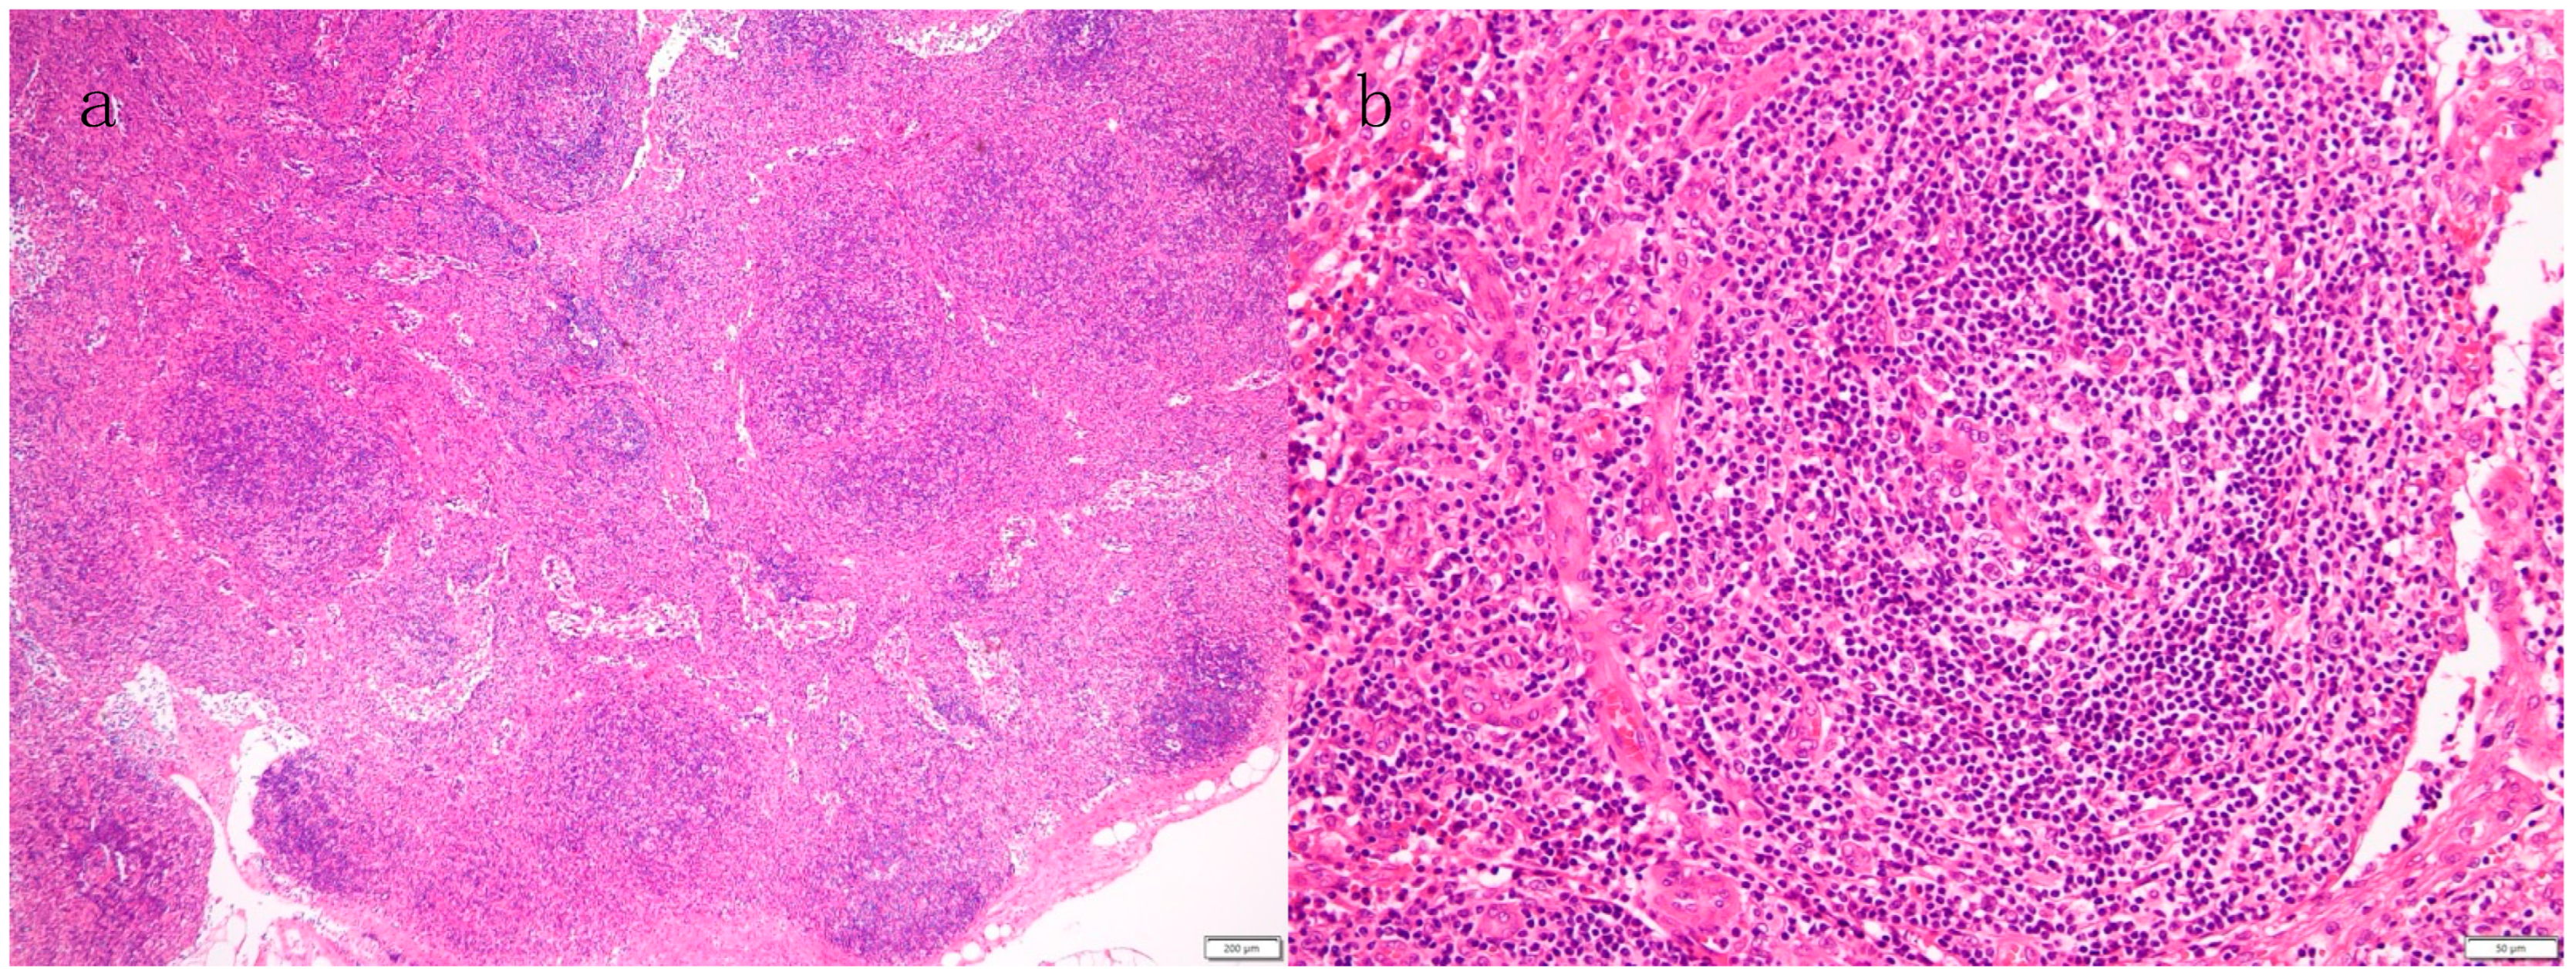

3.2. Histopathological Diagnosis of Lymph Nodes